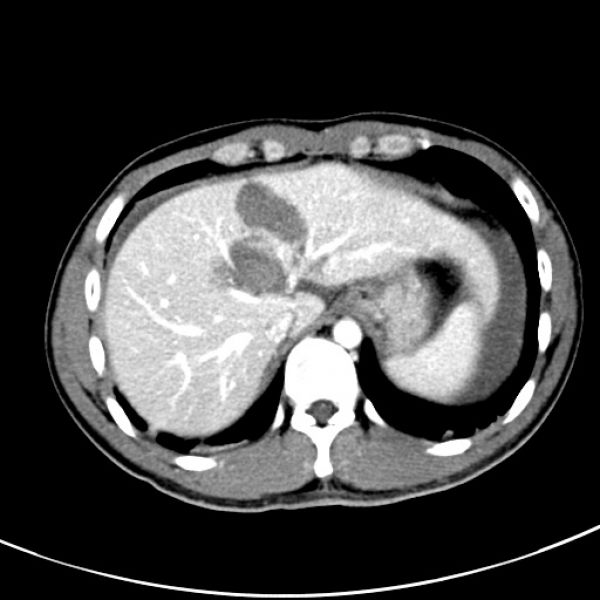

13:10手术开始,腹腔内积血约800ml,吸尽后发现左肝脏面有一长约3cm不规则裂口,不断有鲜血自破口涌出。决定按术前规划实施左半肝切除术,结扎左肝蒂、游离左肝、劈开肝正中裂、移出标本。凭借娴熟的肝脏外科技术,仅仅花费1小时15分钟的时间,顺利完成手术。术中失血估计不超过150ml,术中未输血,病人生命体征平稳。

术后CT(保留肝中静脉)